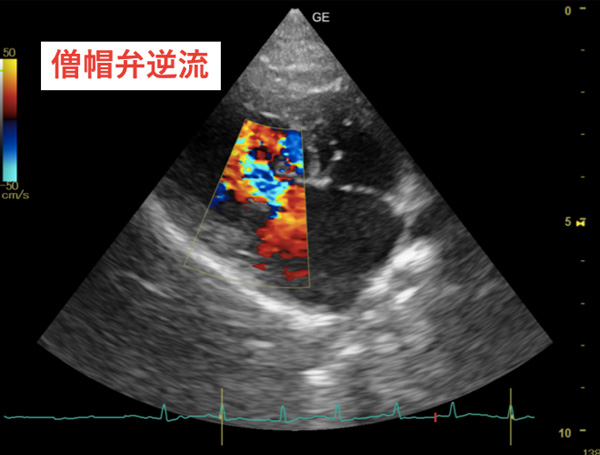

僧帽弁閉鎖不全症

3-4日前からむせるような咳。3回ほど失神のように倒れたことがある。聴診にて左側心基底部よりLevine3/6の心雑音を聴取、X線検査にて左房の拡大を認め、心臓エコー検査にて僧帽弁逆流と、僧帽弁の逸脱、左房拡大を認めたため、僧帽弁閉鎖不全症と診断。

加齢に伴う僧帽弁の粘液腫様変性に基づく弁尖の変形、歪み、逸脱、腱索の伸展や断裂などによって弁尖閉鎖に障害をきたし、収縮期に左心室から左心房に血流が逆流する疾患です。

左心房への血液の逆流の結果、左心房及び肺静脈の圧が上昇し、肺における血液のうっ滞が起こります。この状態が続くと、心臓のポンプ力が低下したり、肺に水が溜まったりします(肺水腫)。